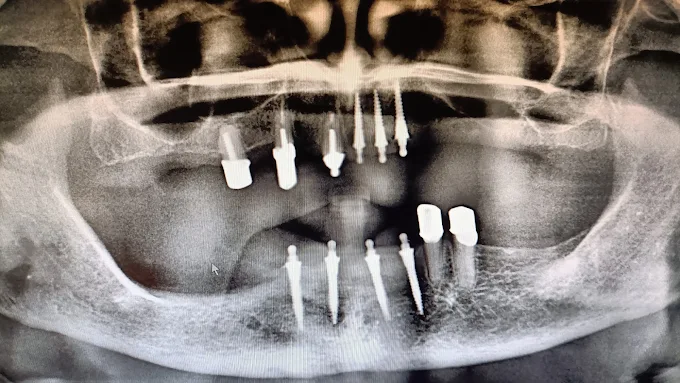

Zahnimplantate aus deutscher und schweizer Herstellung mit bis zu 98% Erfolgsquote, auch ohne Knochenaufbau möglich.

Digitale Röntgentechnik

Maximale Detailschärfe in Sekunden bei minimaler Strahlenbelastung.